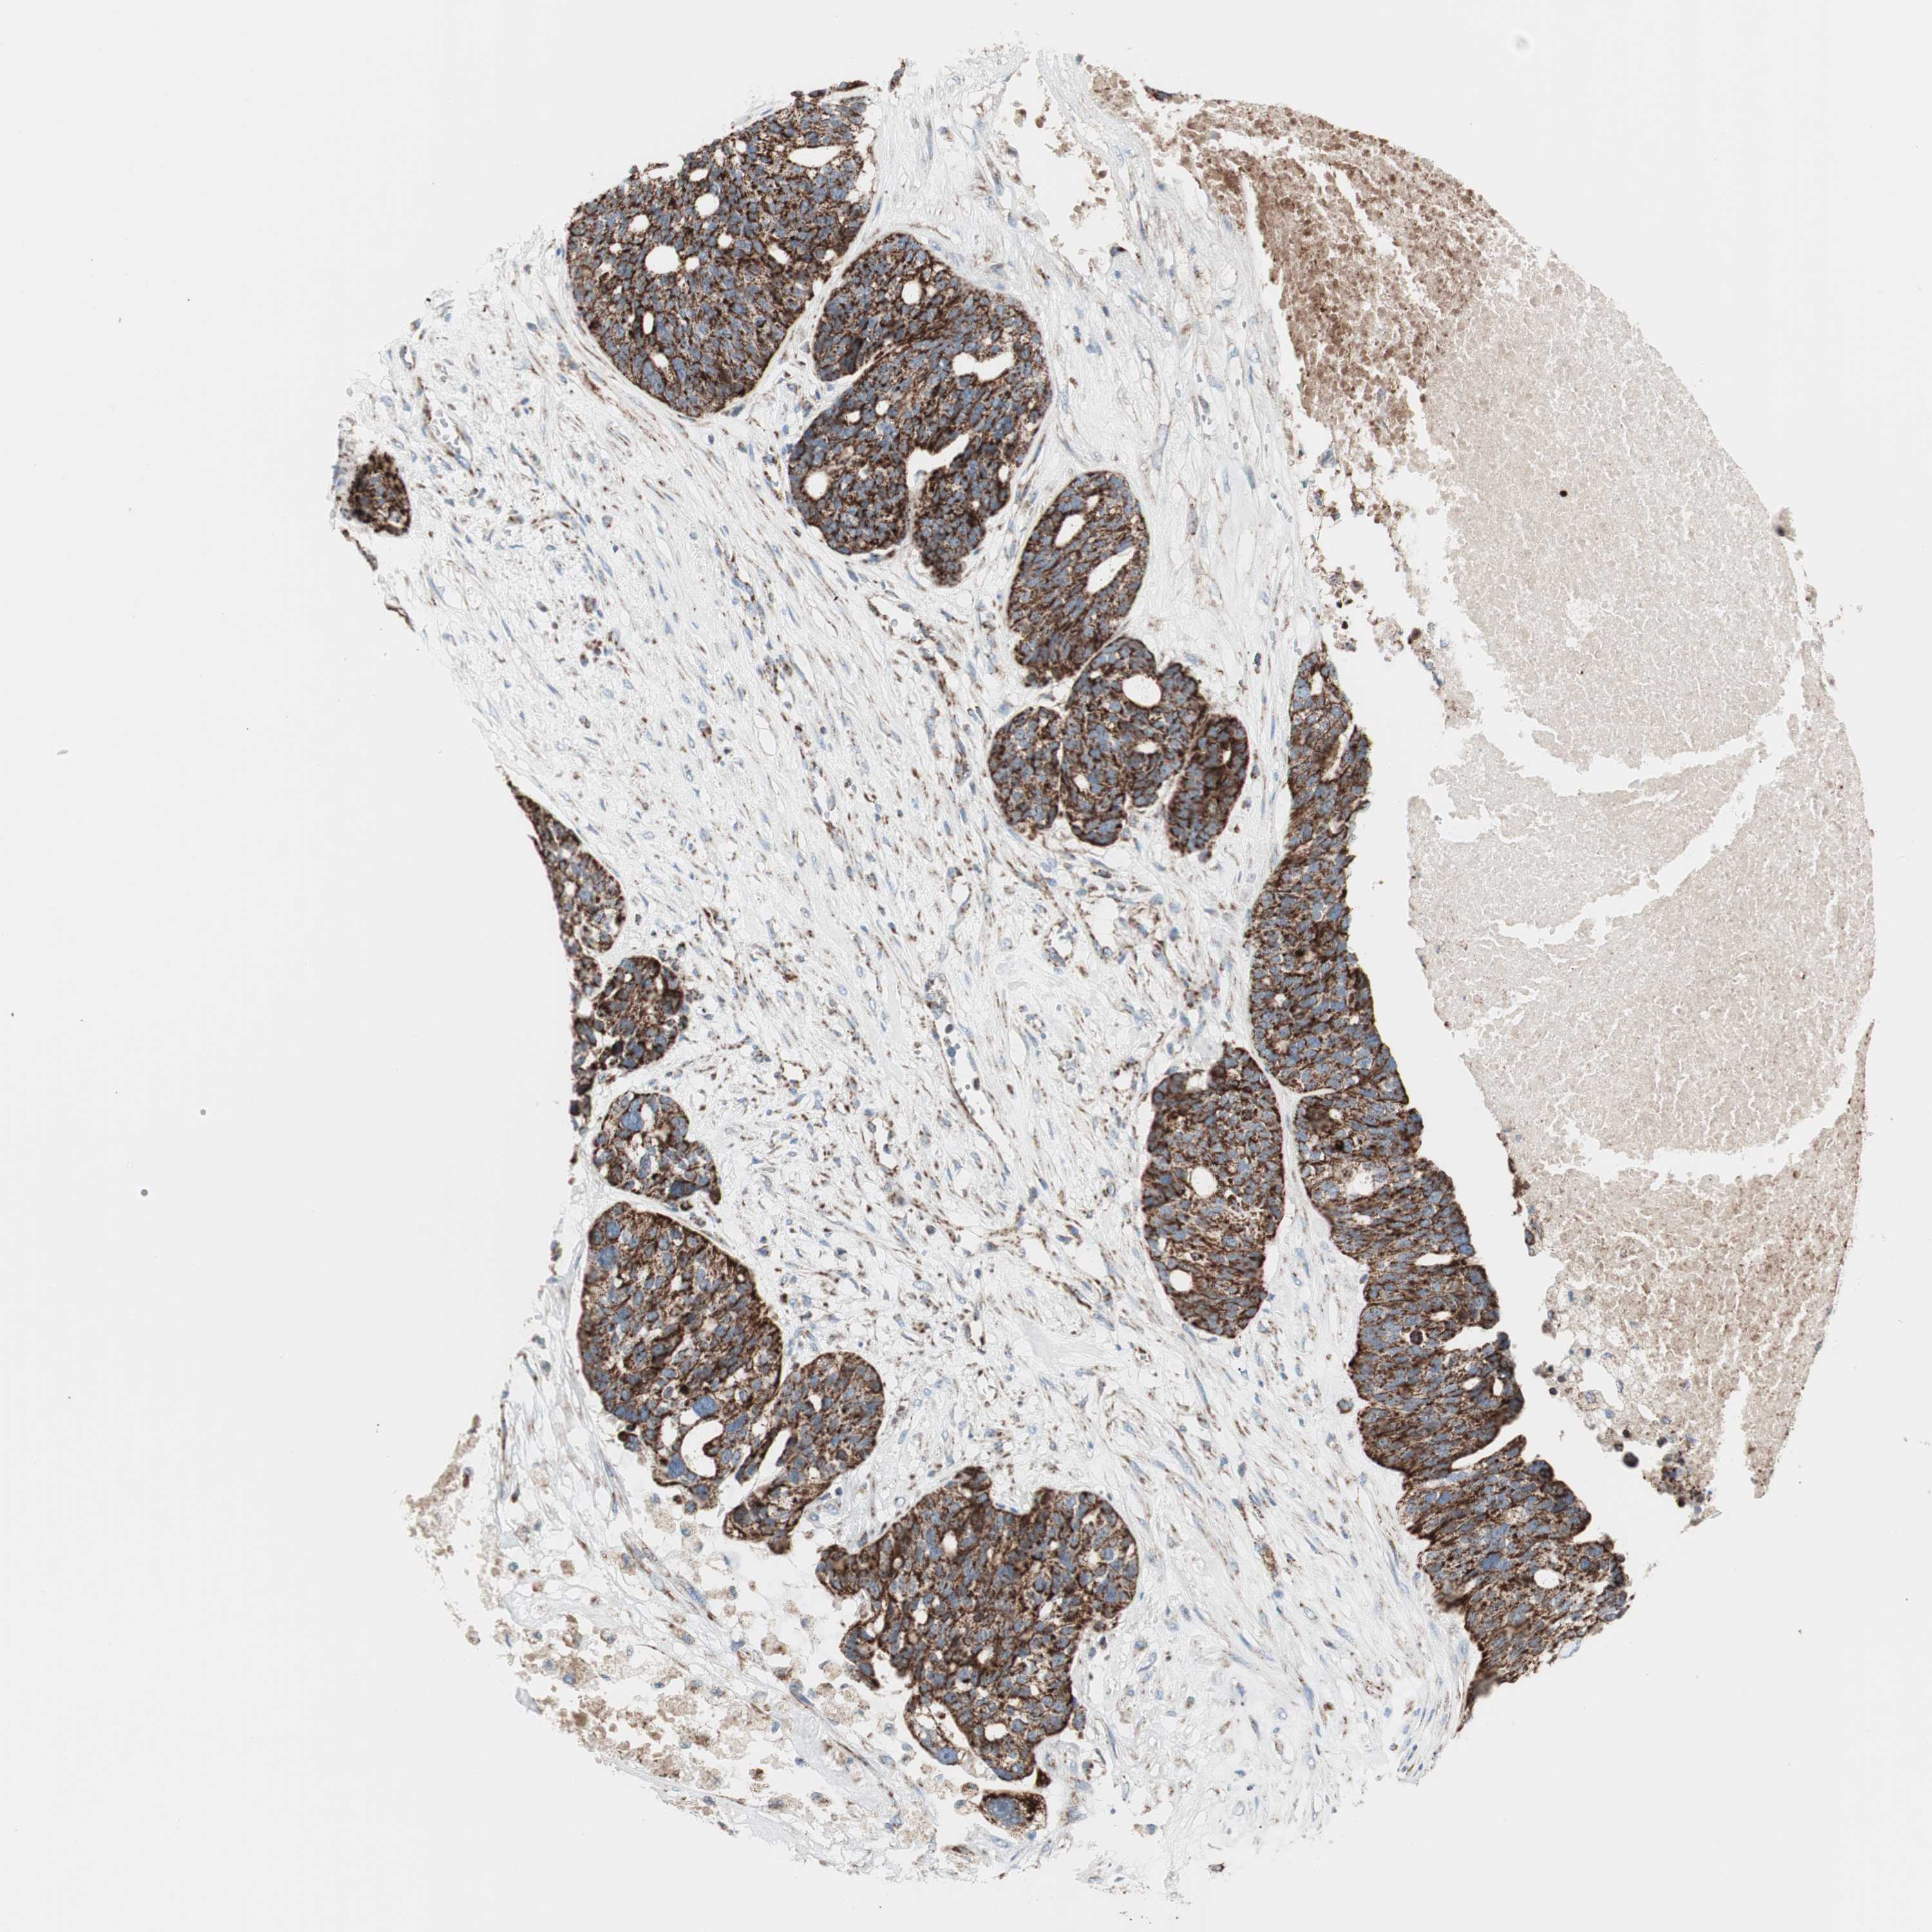

OVARIAN CANCER - Protein expressioni

A mouse-over function shows sample information and annotation data. Click on an image to view it in a full screen mode. Samples can be filtered based on level of antibody staining by selecting one or several of the following categories: high, medium, low and not detected. The assay and annotation is described here.

Note that samples used for immunohistochemistry by the Human Protein Atlas do not correspond to samples in the TCGA dataset.

Antibody stainingi

Antibody staining in the annotated cell types in the current human tissue is reported as not detected, low, medium, or high, based on conventional immunohistochemistry profiling in selected tissues. This score is based on the combination of the staining intensity and fraction of stained cells.

Each image is clickable and will lead to virtual microscopy that enables deeper exploration of all samples and also displays staining intensity scores, fraction scores and subcellular localization as well as patient and tissue information for each sample.

Antibody HPA011562

Antibody CAB005585

Staining

High

Cystadenocarcinoma, serous, NOS

Carcinoma, endometroid

Cystadenocarcinoma, mucinous, NOS

Carcinoma, NOS